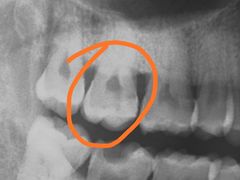

• 爱贝口腔·牙周诊疗·种植修复中心

• -爱贝口腔·牙周诊疗·种植修复中心